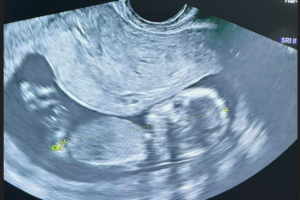

Galería de recuerdos felices Las primeras fotos de Ambar y la historia de sus papás-